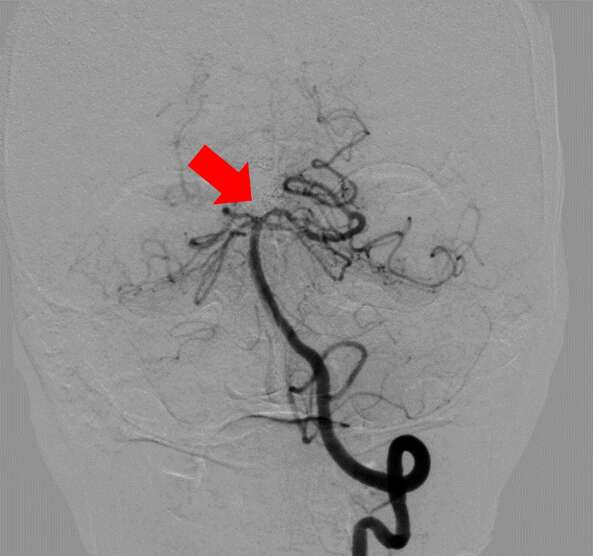

【治療例2:脳動脈塞栓術】

カテーテルを用いて、脳動脈を詰める治療で

す。瘤内部にコイル(金属製の柔らかい針)を幾重にも巻いて血流がなくなるまで詰めていきます。

治療前

赤矢印が脳動脈瘤

治療後

コイルを詰めて血流を遮断